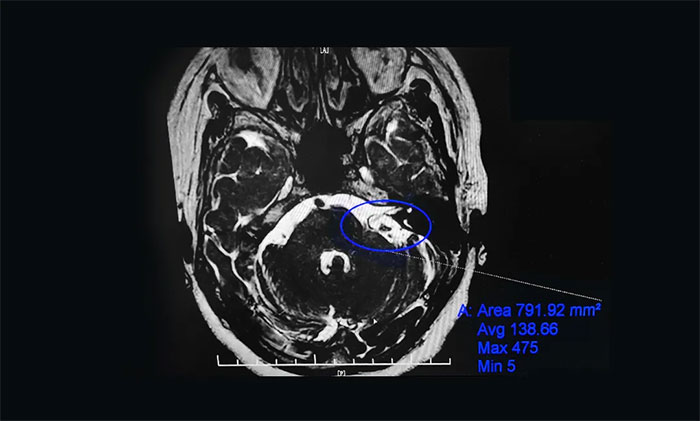

为进一步治疗,刘阿姨在家人陪伴下慕名求医上海蓝十字脑科医院。入院后,杨忠旭教授团队认真评估了刘阿姨面肌痉挛发生的频率、强度和持续时间,并完善了核磁颅神经检查。面神经MRTA+增强显示:左侧面神经与周围小血管关系密切。

▲患者左侧面神经与周围小血管关系密切

术中,在显微镜下见基底动脉走形迂曲并骑跨左侧面神经。在电生理监测“保驾护航”下,杨忠旭教授用特制的器械分离压迫面神经根部的血管,然后放入特制的垫棉将血管与神经隔离开来,解除血管对面神经的压迫。整个手术过程出血少,时程短,术后刘阿姨面部肌肉再也没有抽搐,整个人的精神面貌焕然一新,目前已经康复出院。